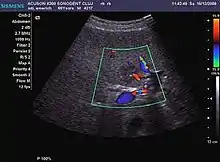

Focal nodular hyperplasia

It is a tumor developed secondary to a circulatory abnormality with abundant arterial vessels having a characteristic location in the center of the tumor, within a fibrotic scar. A radial vessels network develops from this level with peripheral orientation. The tumor's circulatory bed is rich in microcirculatory and portal venous elements. The incidence is higher in younger women and tumor development is accelerated by oral contraceptives intake. 2D ultrasound appearance is a fairly well-defined mass, with variable sizes, usually single, solid consistency with inhomogeneous structure. Rarely the central scar can be distinguished. Spectral Doppler examination detects central arterial vessels and CFM exploration reveals their radial position. CEUS examination shows central tumor filling of the circulatory bed during arterial phase and completely enhancement during portal venous phase. During this phase the center of the lesion becomes hypoechoic, enhancing the tumor scar. During the late phase the tumor remains isoechoic to the liver, which strengthens the diagnosis of benign lesion.